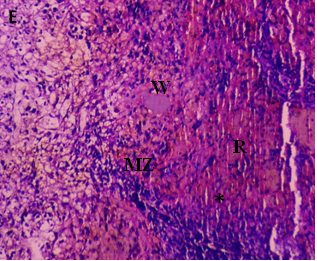

The current investigation focused on spleen histopathology to examine the overall condition of the organ. Elmore (2006), R. E. Mebius and G. Kraal (2005), as well as other sources, were used to anatomize the histopathological differences shown in fig. 114,15. Fig. 1 shows normal histoarchitecture in the control spleen tissue of a male albino rat, with sufficient amounts of red pulp (R), white pulp (W), lymphoid follicles (LF), and marginal zone (MZ). Table 2 has detailed histology observations. The histological structures in the cyphenothrin-treated group were well terminated, just like in the control group. The red pulp in the group that received high doses of the pesticide cyphenothrin showed decreased cellularity, while the white pulp was severely destroyed, with no normal lymphoid follicle and boundary zone. White pulp and red pulp from the low-cure cyphenothrin group showed destroyed cellular integrity. This cyphenothrin-treated group, which included high and low doses, demonstrated notable modifications of histological structures in contrast. In comparison to the cyphenothrin high dosage group, the white pulp recovered effectively in the cyphenothrin insecticide low dose treatment group.

Fig. 1: (A) and (B) Spleen sections of control rats: (R) red pulp; (W) white pulp; (LF) lymphoid follicle; (MZ) marginal zone; (PALS) Periarteriolar lymphoid sheath. H and E, x100. (C) and (D) Spleen structure of rat treated with cyphenothrin (63.6 mg/Kg BW) respectively: arrow head Show a thin damaged marginal zone (MZ), asterisk (*) indicates decreased cellularity (rarefication) and altered structural integrity of white pulp, H and E, 100×. (E) and (F) spleen tissues of cyphenothrin treated (35.33 mg/Kg BW) respectively: arrow shows damaged tissue region, marginal zone (MZ) and lymphoid follicles (LF). H and E, 100